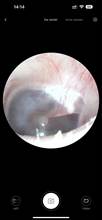

Are you getting sick of useless Q-tips that can’t clean your ears? Also, they can be dangerous because you can’t see where you’re poking at, it’s easy to hurt your ears! So, may I introduce to you the Smart visual ear wax remover, a system to keep your ears clear and safe. With high technology, this product supports HD live streaming over Wifi through our application. It has six ultra-bright LEDs to light up the entire ear canal, promoting perfect visibility and control. Moreover, with five unique brightness levels, this ear cleaner can support crystal clear videos from inside your ears. All of that to make your earwax removal safer than ever. Also, the App supports both iOS and Android devices to connect, so it’s convenient for everybody. Don’t hesitate anymore, get it now!

Rapid WiFi visual connection. No connection is required to open picking ears. Use optical lens and high performance 300W pixel. The CMOS sensor has a clear picture, 20X amplifying ear canal & 55° viewing angle. 13 lens combination & 6 LED lights. IP67 waterproof lens. Water washable. Adapt to dry ear, oil ear and other complex environment. 3 axis smart directional gyroscope quick positioning, screen is not bias & shake. High-end OV chip video coding technique, hand-eye synchronous exciting picking! Strong WiFi signal, penetrating power, avoid delay. More safety protection. Earpick head buckle, over-hot earpick protection, timing automatic shutdown, children lock and anti frost cracking protection. Smart constant temperature control. Prevent low temperature & ear burning . Otoscope: 25°C non-inductive temperature. Earpick body: 32°C palm’s temperature. Long endurance. Built-in 250mAh large capacity battery. Picking once a week for 10 minutes, can use about 30 days.